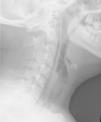

Presentamos el caso de una adolescente de 14 años, valorada en el Servicio de Urgencias Pediátricas por dolor y crepitación de aparición brusca a nivel cervical derecho, tras haber presentado un acceso de tos. Asociaba cuadro de fiebre, máximo 39°C, de 24 h de evolución, junto con odinofagia. No refería antecedentes personales de interés ni cuadros previos de broncoespasmo. La paciente presentaba un triángulo de evaluación pediátrica estable sin signos de dificultad respiratoria. En la exploración se objetivaba crepitación cervical y faringe hiperémica sin exudados, con úvula centrada y pilares no abombados. La auscultación pulmonar era normal, con saturación de oxígeno del 95%. La analítica sanguínea no mostraba alteraciones y el test faríngeo para Streptococcus pyogenes fue negativo. Se realizó una radiografía de tórax, con espacio neumomediastínico y campos pulmonares normales, observándose en la radiografía lateral de cavum la presencia de enfisema retrofaríngeo y subcutáneo, aunque sin aumento del espacio retrofaríngeo (fig. 1). Se solicitó valoración por Otorrinolaringología, que realizó laringoscopia indirecta sin hallazgos patológicos, por lo que ingresó con oxigenoterapia, analgesia y monitorización con el diagnóstico de sospecha de enfisema retrofaríngeo espontáneo.

Respecto a las pruebas complementarias, la radiografía de tórax y lateral del cuello confirmará el diagnóstico; los hallazgos analíticos, como leucocitosis con neutrofilia y aumento de reactantes de fase aguda, pueden orientarnos hacia una infección retrofaríngea1. La realización de una tomografía computarizada puede estar indicada para ver la extensión del enfisema y descartar colecciones y/o mediastinitis5.